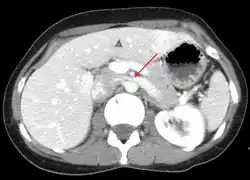

Compression of the left renal vein (marked by the arrow) between the superior mesenteric artery (above) and the aorta (below) due to nutcracker syndrome